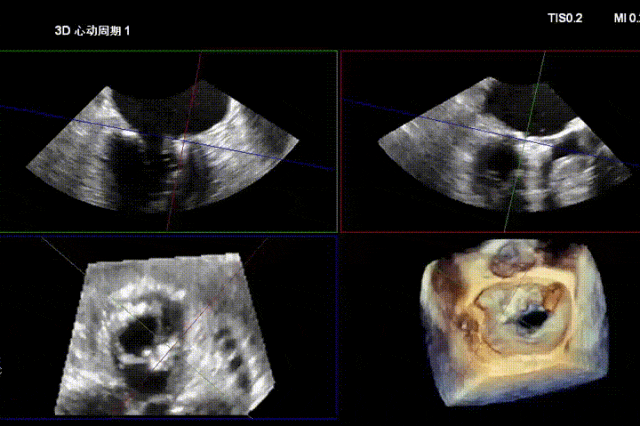

术前经食道超声显示:二尖瓣C1、P1区脱垂,重度关闭不全,彩色多普勒提示大量二尖瓣反流。术前瓣口面积MVA约5cm²,瓣环前后径AP约36.9mm,前叶A1约26mm,后叶P1约15.2mm。